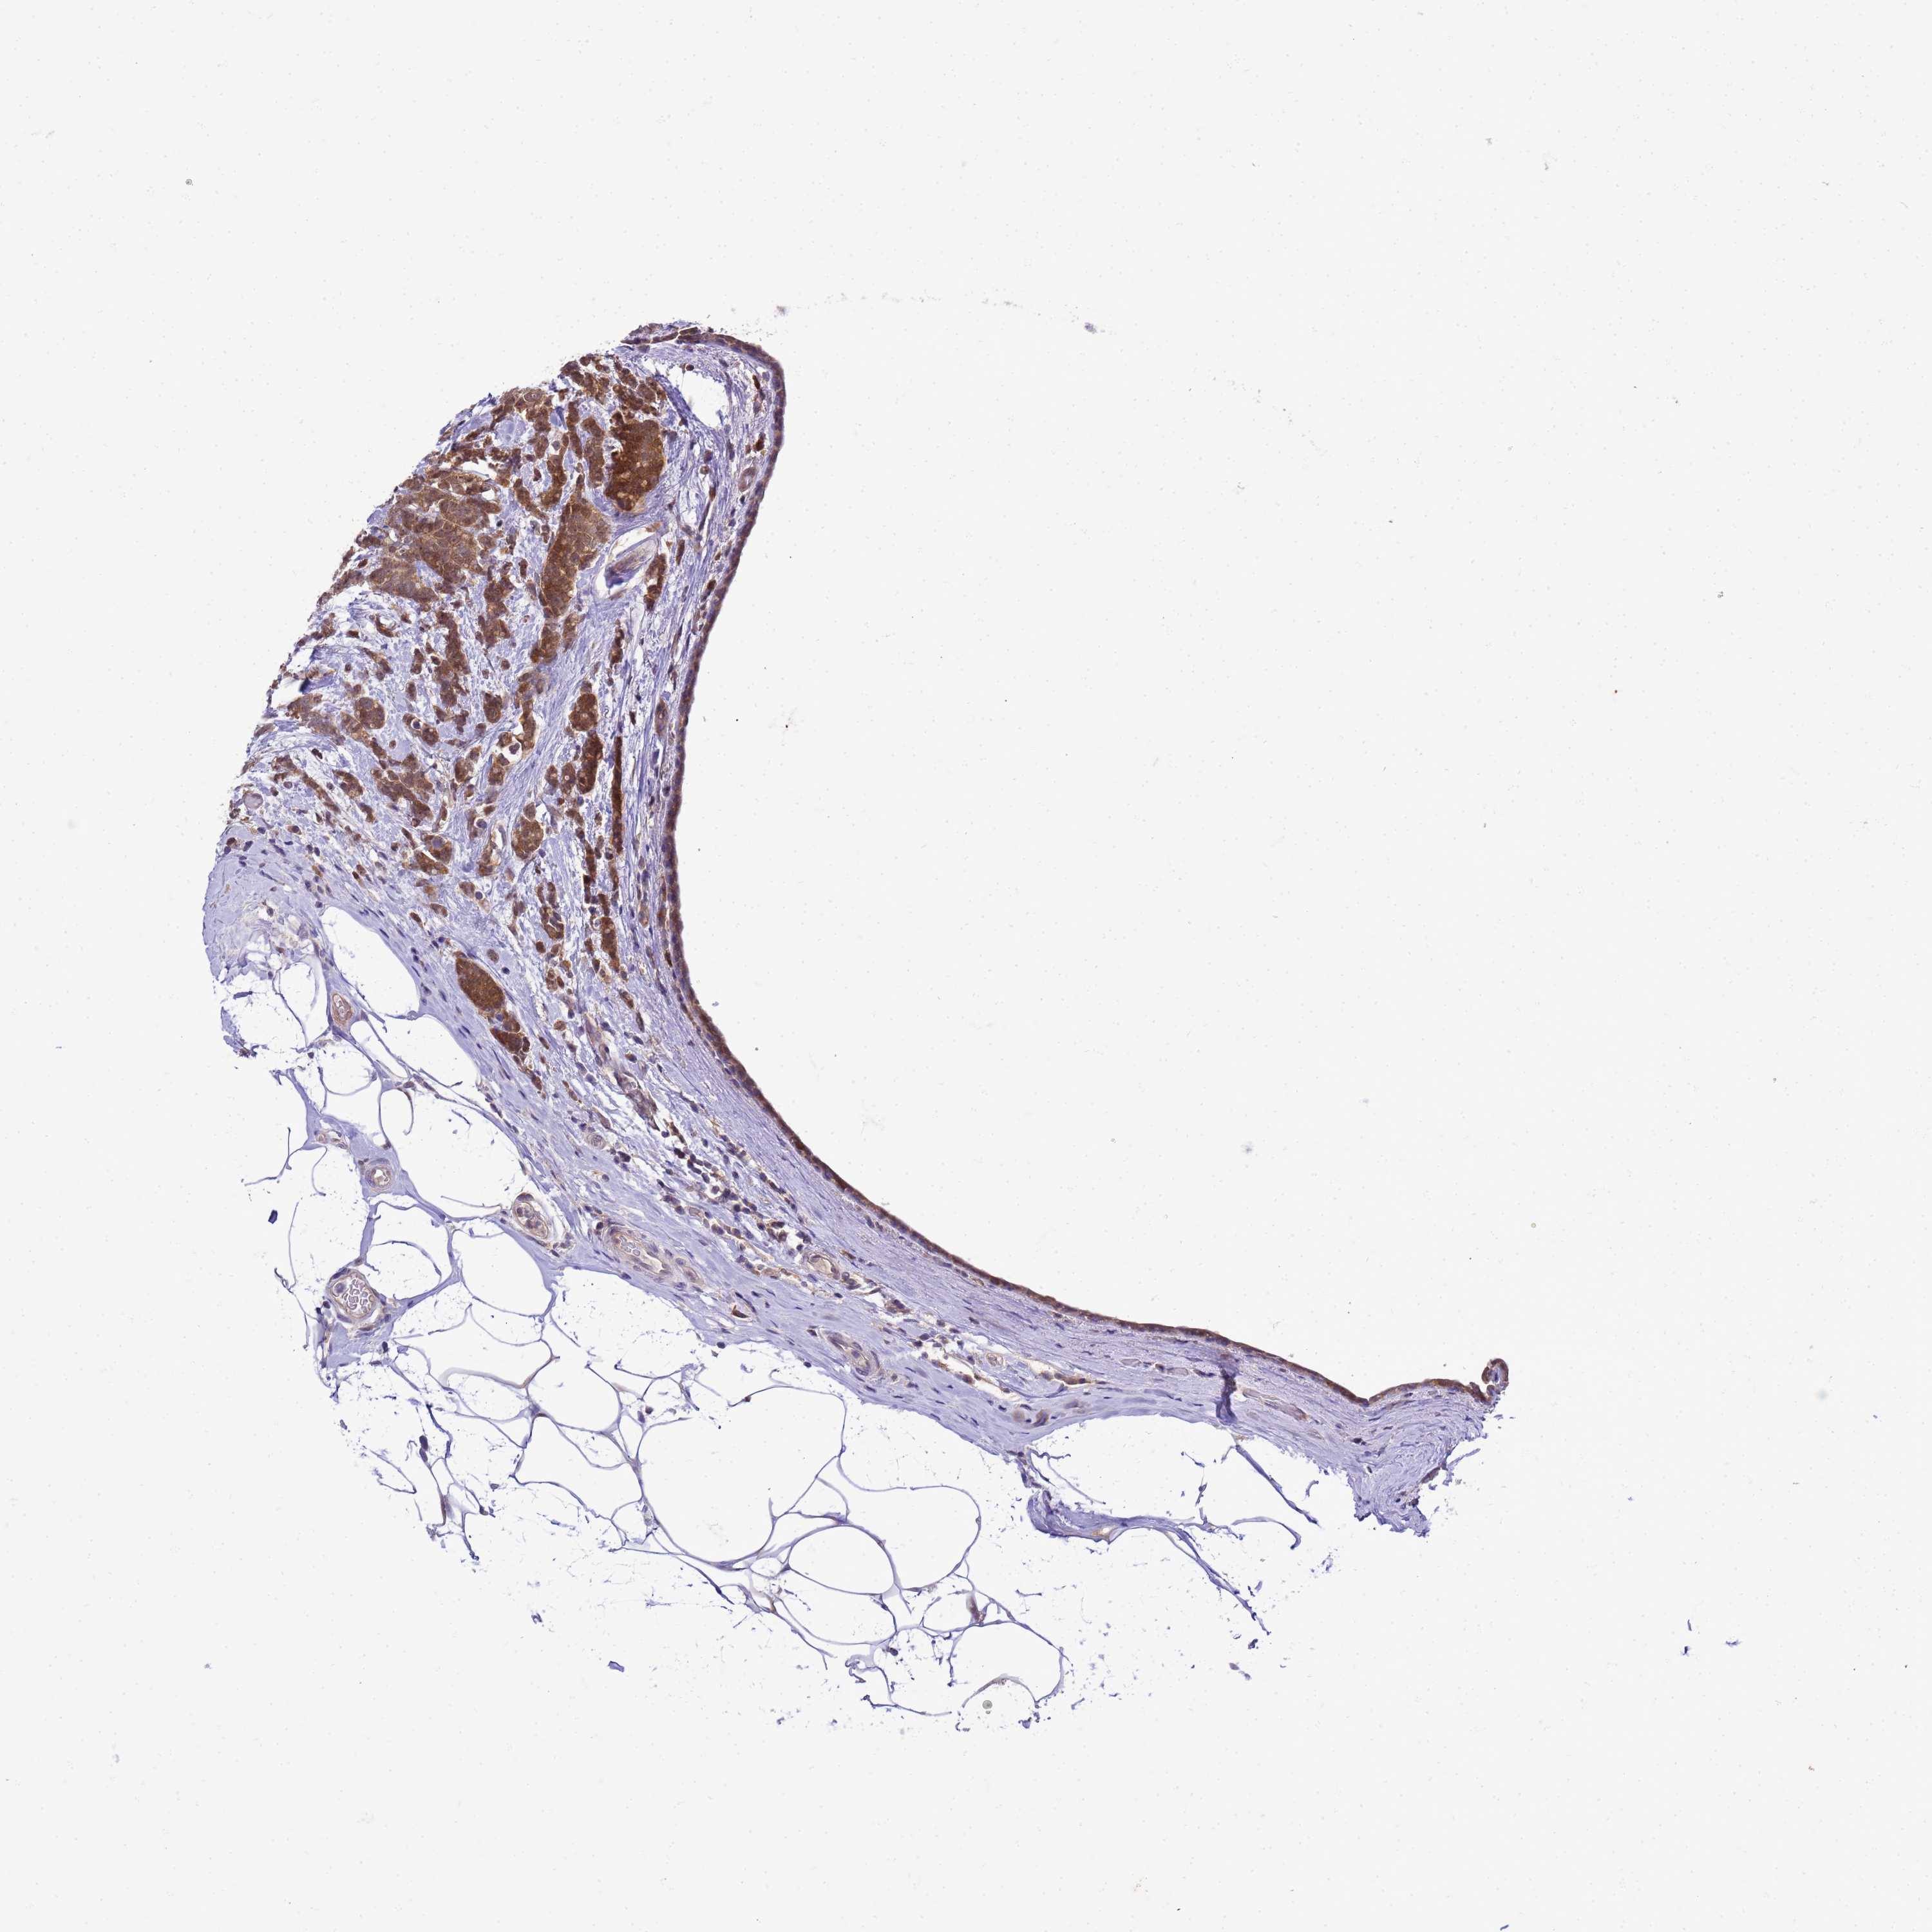

CANCER BREAST CANCER Show tissue menu

BRCA TCGA BRCA VALIDATION PROTEIN EXPRESSION

ANTIBODIES

AND

VALIDATION